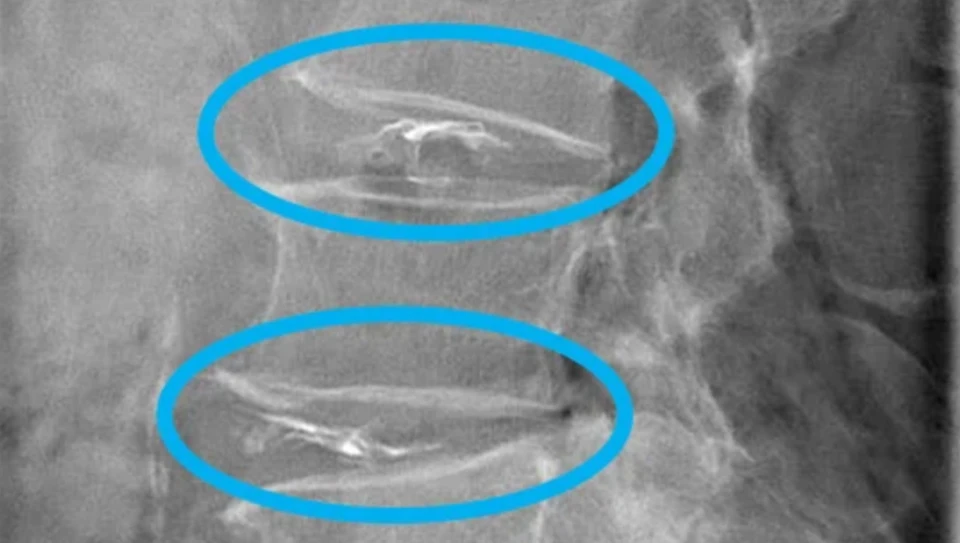

タングステンという金属は、X線を透過しにくい物質です。そのため治療中にディスコジェルが椎間板の中にちゃんと入ってるか確認することが可能です。

X線を吸収する、X線を通さないということです。画像上は白く写ります。

タングステンがX線を通さないことの良い点は、治療の途中やその後もディスコジェルの位置が正確に確認出来ることです。